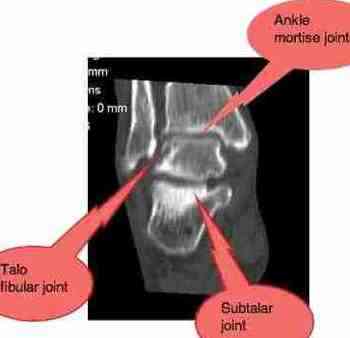

If you do nothing, immobilisation arthritis will set in, and it'll look like the enclosed scan in a few years time.

It's probably in the ankle mortise joint, or the subtalar joint, but could be any one of many. A careful, thorough examination is called for and, like I said, I think it's likely to be routine to fix. Don't sign up for thirty treatments! Not in this instance, nor ever.